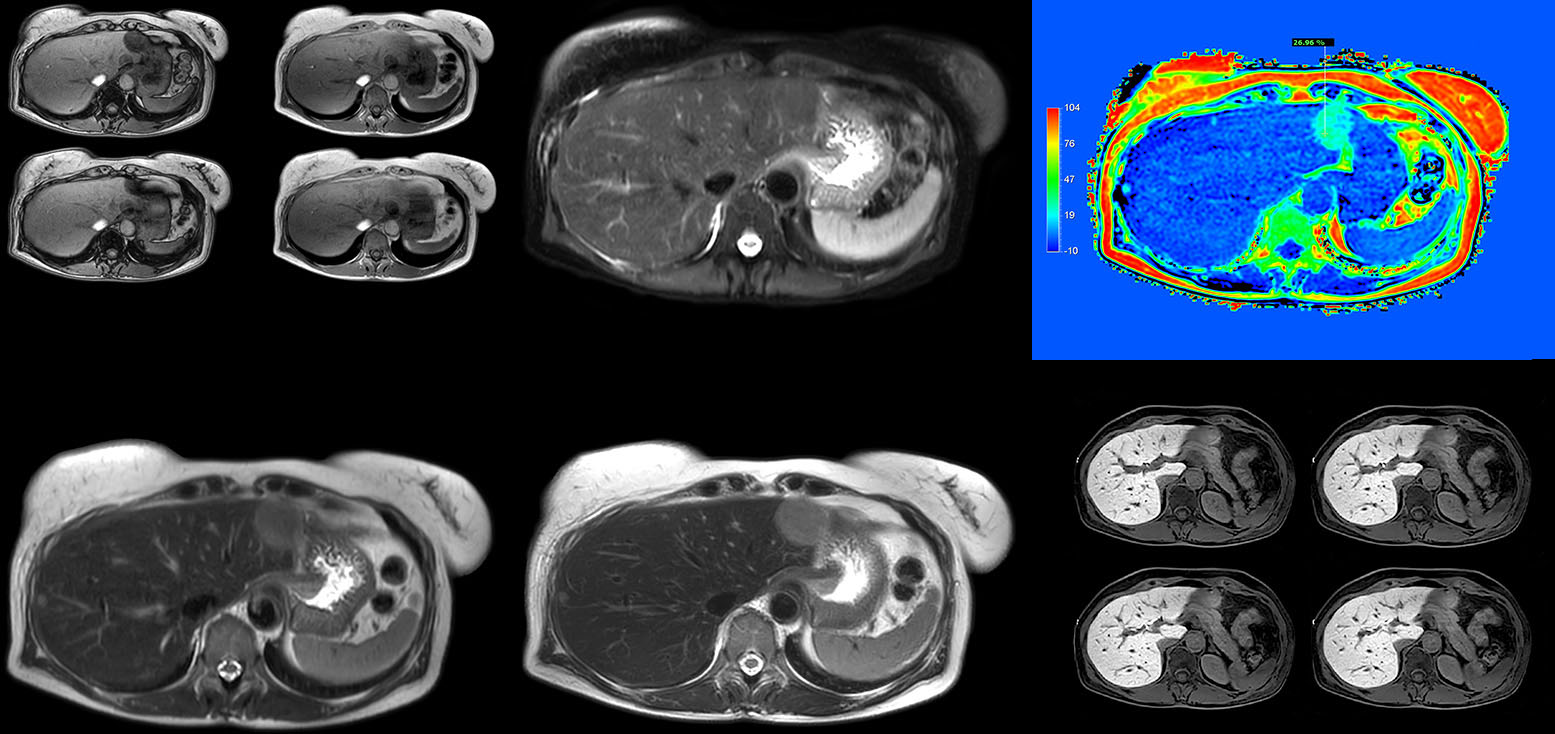

Dr. Kukuk’s liver exam begins with T2-weighted imaging, single shot and with fat suppression. “We always perform diffusion weighted imaging (DWI) with four b-values (0, 50, 250, 800) for lesion characterization, for monitoring after therapies, and for visualization of small lesions. Before giving contrast we routinely use the mDIXON Quant fat quantification sequence. Then we use dynamic e-THRIVE with an in-plane spatial resolution of 1.5 mm and high temporal resolution in just four breathholds of 13.1 seconds.” “Contrast enhancement is important to help us characterize lesions, for follow up in oncology patients and to inform clinicians when deciding on possible changes in the therapeutic regimen,” Dr. Kukuk explains. “Because we use liver-specific contrast agents we can obtain the T2-weighted images after the dynamic, to bridge the waiting time needed with these contrast agents. Just before the patient leaves the scanner we acquire another e-THRIVE in the axial plane and one or two coronals.”

“We have performed a study comparing mDIXON Quant fat percentages with results from histopathology. The correlation with different histologic methods was very good and also the correlation with MR spectroscopy was far above 0.9 – a nearly perfect correlation,” says Dr. Kukuk.

“Fatty liver disease is a common condition. Studies found a prevalence of non-alcoholic fatty liver disease in up to 44% in the general European population [1]. Liver fat cannot be quantified by ultrasound or CT, so biopsy has been the way to quantify fatty liver disease so far,” says Dr. Kukuk. “mDIXON Quant now allows non-invasive quantification of liver fat, which is valuable for both diagnosis and follow-up during dietary changes or therapy, for instance in hepatitis C.”

“The mDIXON Quant fat fraction maps provide quantitative information and also anatomical detail. The sequence is fast, usually taking about 16 seconds, which is just a breath hold for most patients. It definitely improves our efficiency.”